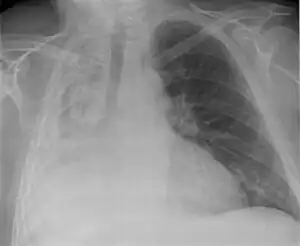

| Left tension pneumothorax with a large, well-demarcated area devoid of lung markings with tracheal deviation and movement of the heart away from the affected side. |

Tension pneumothorax

Tension pneumothorax is an emergent condition in which air gets trapped in the space between the chest wall and the lung. This space is referred to as the pleural space. Because air can't escape from this space, the air pocket grows larger and larger, resulting in the lung collapse closest to the pneumothorax. Forces are transmitted to the mediastinum and effectively "push" the mediastinal structures to the opposite side of the chest.[5]